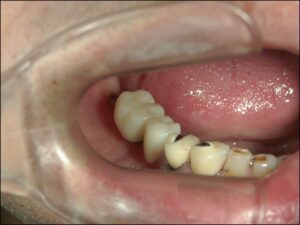

↑術後約3か月で最終的な歯が入りました。